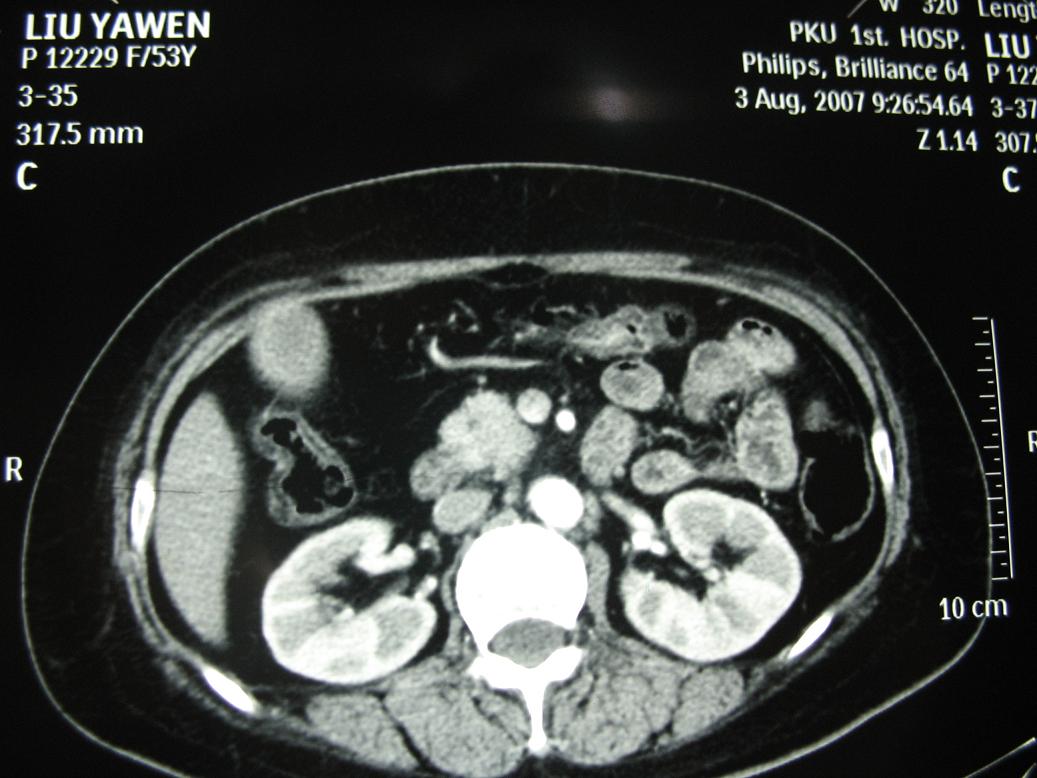

标题: CT17151:女 53岁 腹痛数月余 轻微黄疸 [打印本页]

女 53岁 腹痛数月余 轻微黄疸

1)考虑胰头癌。2)胆囊炎。

壶腹周围占位(钩突ca?)

胰腺钩突mt

支持胰腺钩突ca伴胆系梗阻,胆囊炎

考虑 胰头癌可能性大。